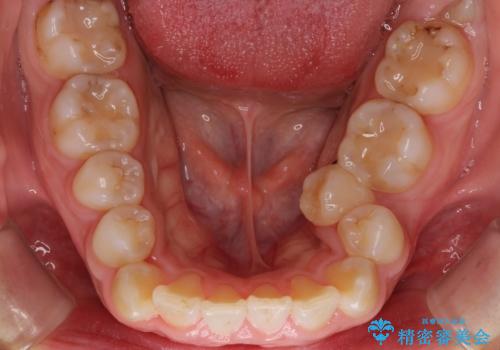

- ガタガタと出っ歯を主訴に来院されました。

上下左右の歯を1本ずつ、合計4本抜歯してワイヤーにて矯正治療をすることとなりました。

前から4番目の歯を抜歯することが多いのですが、右上の前から5番目の歯が神経の治療済みであり、こちらの歯を抜歯する計画としました。

通常より治療期間を要しましたが、健康な歯を残すことができました。